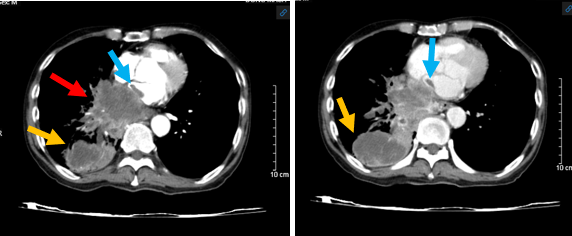

Hình 1: Hình ảnh chụp cắt lớp vi tính ngực – bụng: U vùng rốn phổi phải (mũi tên đỏ) xâm lấn tâm nhĩ trái (mũi tên xanh) nghi ngờ huyết khối buồng nhĩ trái và u thùy dưới phổi phải (mũi tên màu vàng cam).

Kết luận: Hình ảnh khối u vị trí rốn phổi phải và thùy dưới phổi phải, xâm lấn nhĩ trái gây huyết khối buồng nhĩ trái, xâm lấn thực quản, cơ hoành, nhu mô gan phải. Nốt đặc rải rác phổi trái, hạch trung thất, nốt tuyến thượng thận trái – theo dõi tổn thương thứ phát. Giãn phế nang rải rác nhu mô phổi 2 bên.